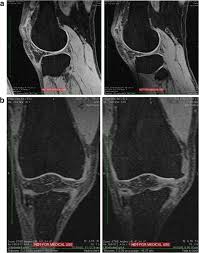

Knee Synovitis Rheumatoid Arthritis Radiology Case Radiopaedia Org

Knee Synovitis Rheumatoid Arthritis Radiology Case Radiopaedia Org from prod-images-static.radiopaedia.org

The mri can take between 20 minutes and 1 hour, depending on the body part. A doctor is trained for over 11 years (many specialists are trained even longer) to make the right decisions on behalf of patients. Mri results are usually available to a doctor within one to two days, reports webmd. An mri scan can take between 15 to 90 minutes depending on which part of your body needs to be scanned. An mri exam is a painless procedure. Most knee mri scans take about 30 minutes,. If someone urgent is found, they will usually get an urgent notification. A knee mri (magnetic resonance imaging) scan uses energy from strong magnets to create pictures of the knee joint and muscles and tissues.